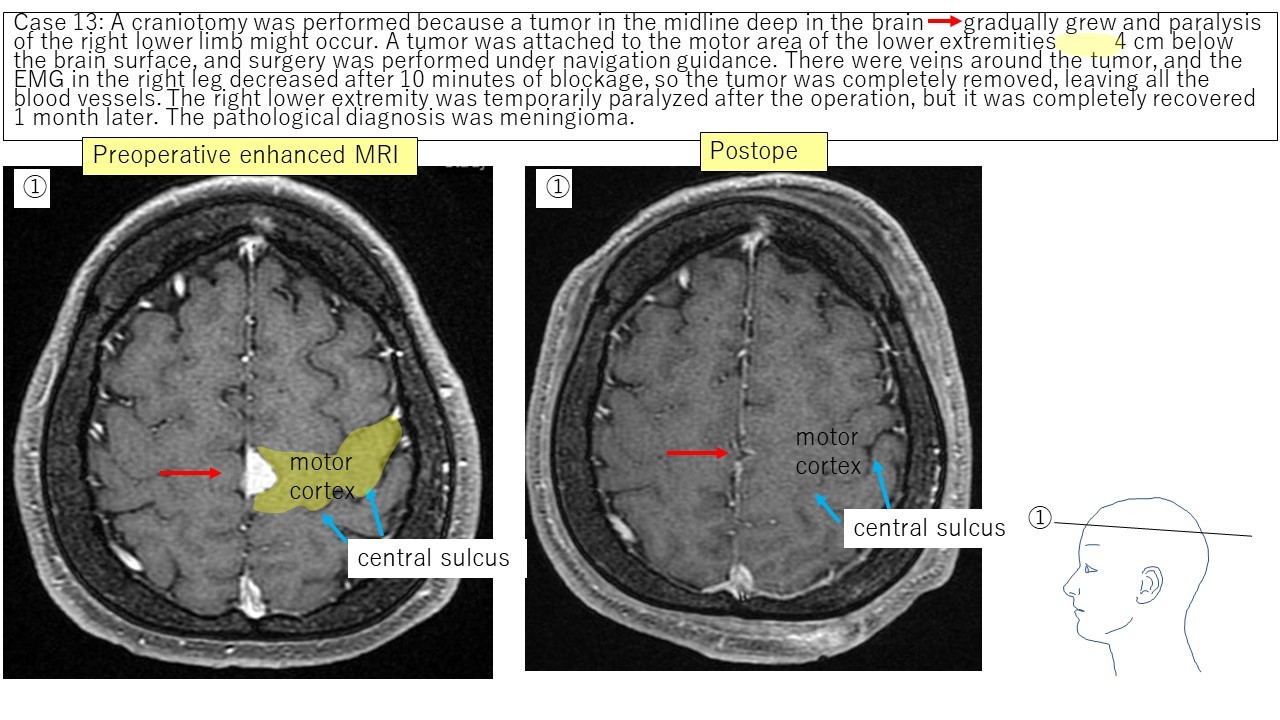

Falx meningioma Case 13 Case 14